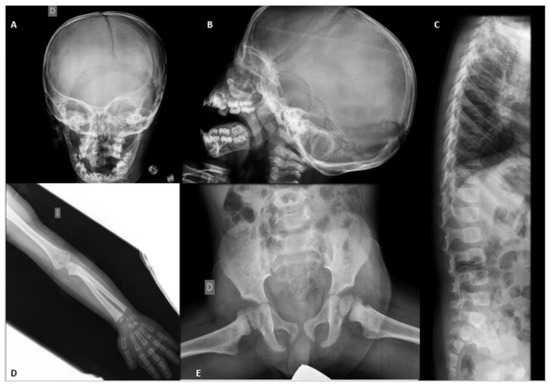

2. Patient Information

3. Musculoskeletal Features